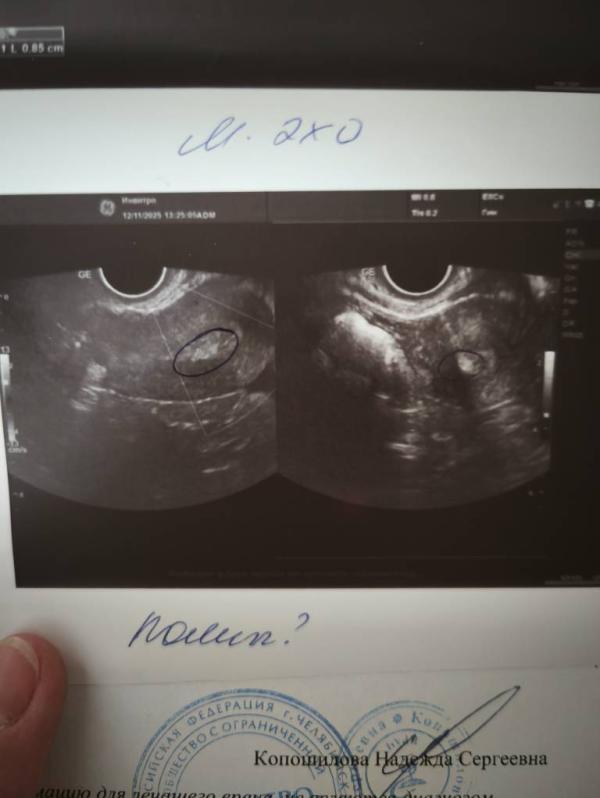

Прошлый цикл был хороший эндометрий, неудачный крио. В этом цикле на 5 день был прекрасный эндометрий, сейчас пошла подтвердить овуляцию и как гром среди ясного неба опять подозрение на полип.